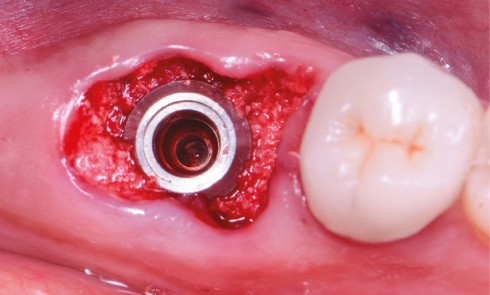

Article réservé à nos abonnés L’extraction implantation immédiate en secteur postérieur associée à la mise en œuvre du pilier SSA

Depuis plusieurs années, l’extraction implantation immédiate apparaît comme une stratégie de traitement arborant un nombre fleurissant de publications scientifiques [1,...